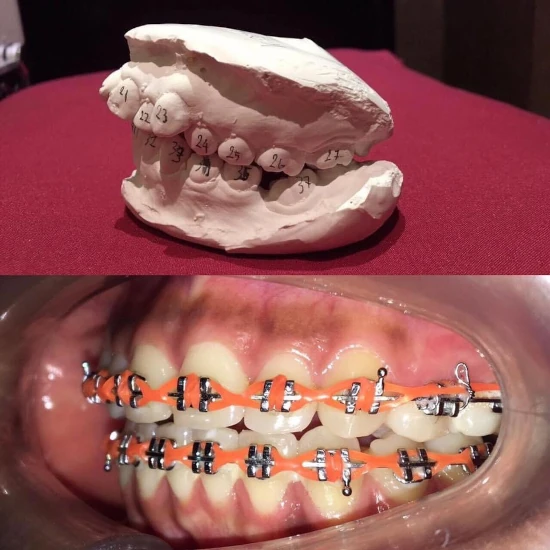

ลูกค้าจัดฟันทำฟัน

| จัดฟันแบบโลหะ | 36,000-45,000/เซต |

| รีเทนเนอร์ | 2,000-2,500/ชิ้น |

| Viera Retainer | 3,000/ชิ้น |